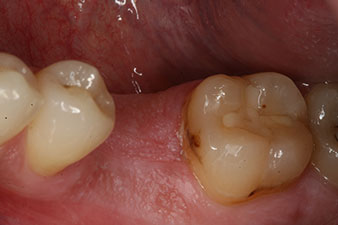

Situación clínica inicial

Figura 1: Situación clínica inicial después de la cicatrización del alvéolo de extracción de la pieza 36: la base del hueso es ancha y existe una cantidad suficiente de encía queratinizada.

En el paciente de 28 años con un historial de fumador severo, fue preciso extraer la pieza dental 36 como consecuencia de una recidiva de una periodontitis apical.

Como las piezas dentales adyacentes estaban en su mayoría intactas, el único tratamiento posible para los huecos existentes era un implante.